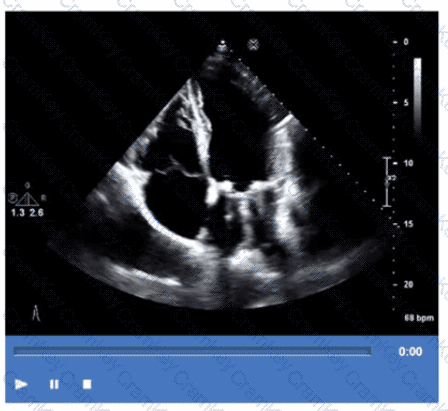

Which patient positioning is best for obtaining the waveform seen in this image obtained by a non-imaging transducer?